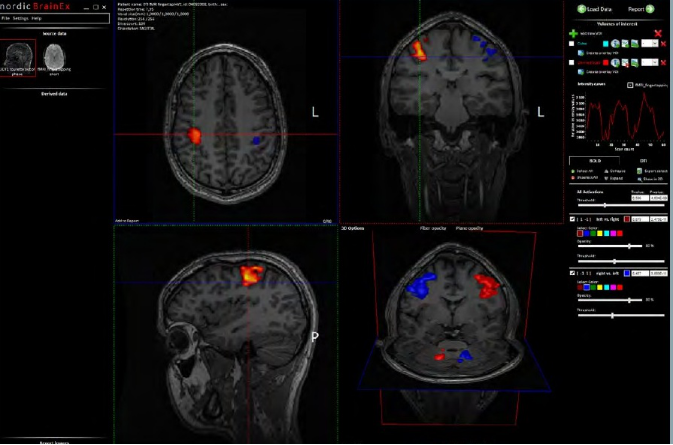

NordicBrainEx是專爲臨床設計的fMRI後處理軟件。簡易而功能強大的界面提高瞭(le)用戶的工作效率。先進的感興趣體積工具、BOLD激活區域的2D/3D可視化、DTI纖維追蹤成像和灌注MRI圖讓臨床醫生可對病竈周圍區域的大腦組織進行廣泛且深入的評估。(對於(yú)腫瘤的分類,分級,術中導航以及治療後的跟蹤監測有重要作用)

2.高效的GLM(一般線性模型)分析,可以在同一窗口中顯示大量的BOLD fMRI序列,包括2D/3D圖(tú)和阈值的設(shè)置。

BOLD fMRI 模塊